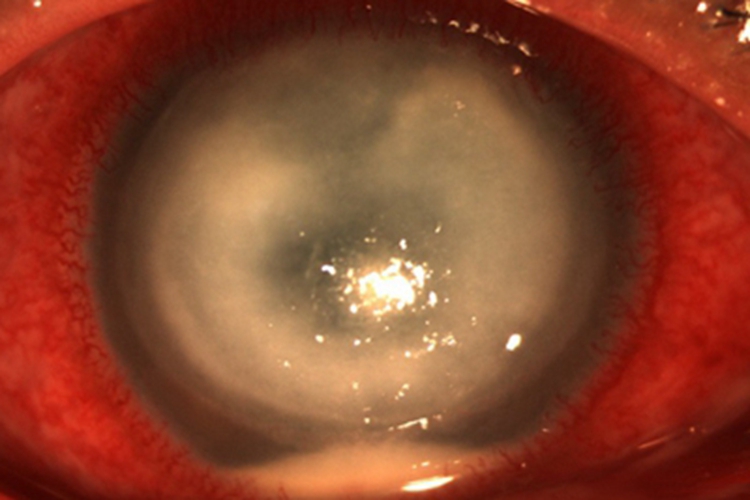

角膜挫伤患者可有明显的眼部疼痛、畏光、流泪及眼睑痉挛等症状,视力也受到影响。上皮缺损区荧光素着色,若发生感染,可出现角膜水肿、增厚以及大小不等的白斑,可引起角膜溃疡。

角膜挫伤可遵医嘱涂红霉素眼膏治疗,如果上皮缺损面积较大,或伴有前弹力层损伤者,可加用角膜上皮生长因子,双眼包扎。对于角膜水肿严重的患者,在角膜上皮愈合后,可在医生的指导下应用糖皮质激素滴眼液滴眼,减轻水肿。